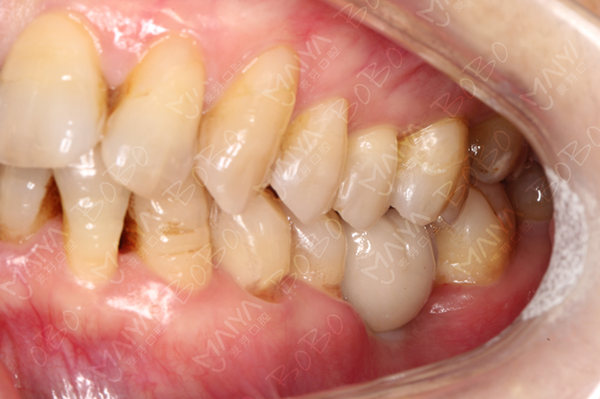

种牙完成后的牙齿

术后口腔全景ct

麦芽口腔种植医师团队对赵阿姨的情况全面分析,为其量身定制麦芽MAC数字化精确种植牙,通过模拟导航把握种植角度,深度,吻合度,准确快速找到最佳植入位置,稳固耐用可超过几十年。赵阿姨不停点赞:"儿子打电话帮我预约的,今天早早便催我出发,不忍辜负儿子的一片孝心,所以今天就过来了,没想到这里的条件这么好,医护人员都很热情很专业,环境一流,技术一流。"